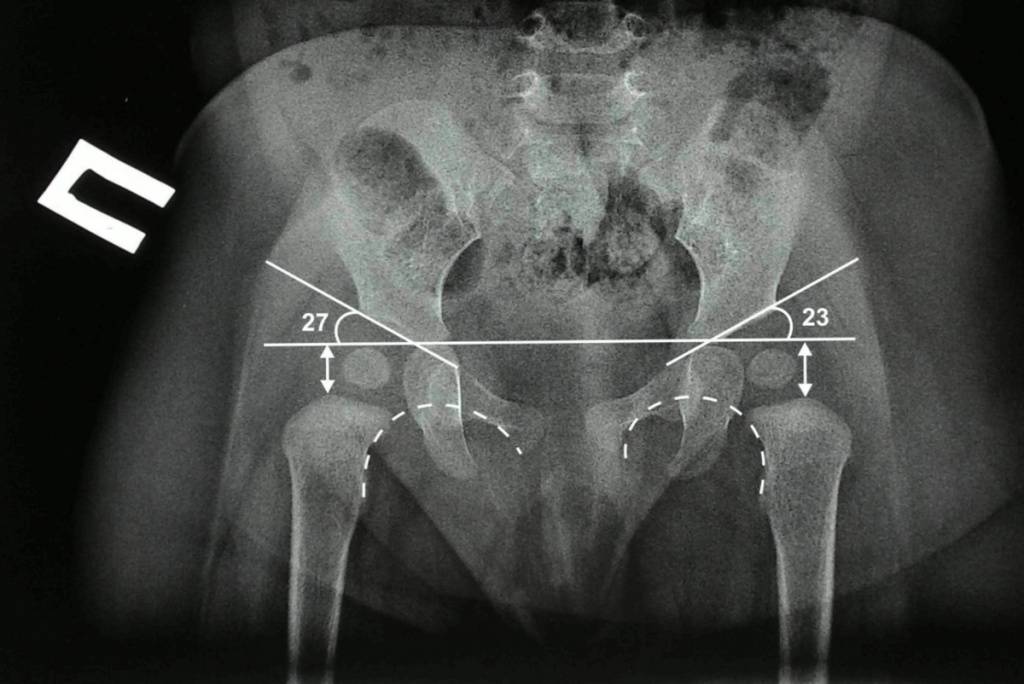

У новорожденных вертлужная впадина и большая часть бедренной головки представлены хрящевой тканью, поэтому на рентгенологических снимках не видны. Для трактовки результатов используют различные схемы с проведением специальных линий, чтобы рассчитать угол наклона крыши вертлужной впадины. В норме он должен быть не меньше 30° у новорожденных и примерно 20° – у малышей от трех месяцев и старше.

Также во время осмотра новорожденных врач проверяет подвижность суставов. При отсутствии патологии ножки младенца отводятся до положения 80-90°. У детей с дисплазией угол не превышает 50-60°.

Основным методом диагностики является ультразвуковая диагностика. В 2-3-месяца врач может назначить рентген. До этого времени такую диагностику не используют из-за низкой информативности. У новорожденных большую часть сустава формирует хрящевая ткань, которая на рентгене не отображается.